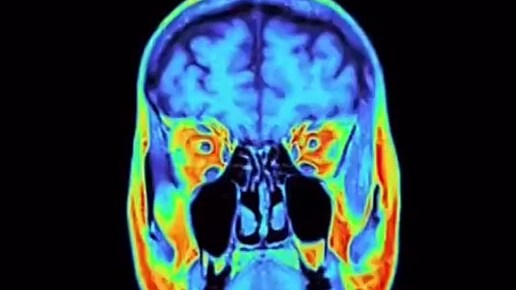

Как выглядит ваш мозг и...

О здоровье: с медицинского на русский